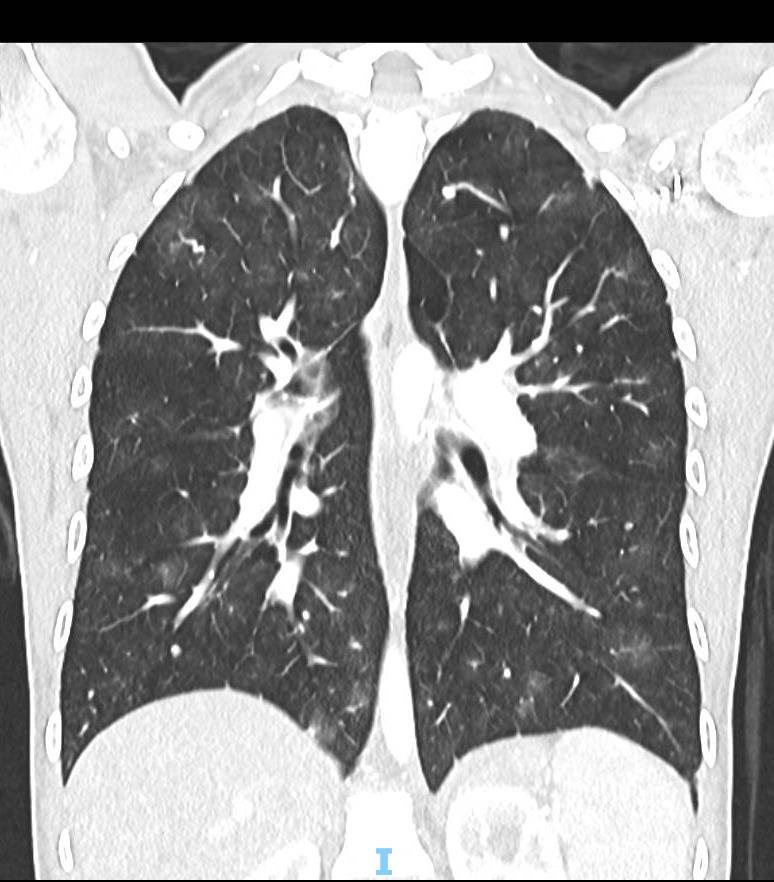

Acute Pediatric COVID-19: CT

21 Imaging of Covid 19 infection in children

3 Phases

Early: "Halo" sign

Local infection

Progressive: Diffuse GGO

Developed: Consolidation

Surr vasc congestion

Inflammation - adj alveoli

Alveoli fill with fluid/cells

• Bilateral & multifocal GGO, +/Consolidations or both

• Halo sign

• Peripheral and subpleural

• Bronchovascular thickening